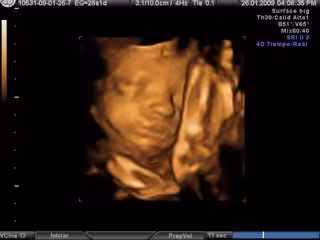

Ecografía en 3D- embarazo

Foto: EUROPA PRESS

Una mujer australiana ha sido imputada por fraude tras vender ecografías falsas a numerosas mujeres embarazadas. La mujer descargaba imágenes de ecografías en 4D de Internet para luego venderlas a mujeres embarazadas.

La sospechosa hacía pasar esas imágenes descargadas por fotos de niños en el útero de sus clientes en la ciudad australiana de Bunbury, según ha publicado el diario británico 'Daily Mail'.